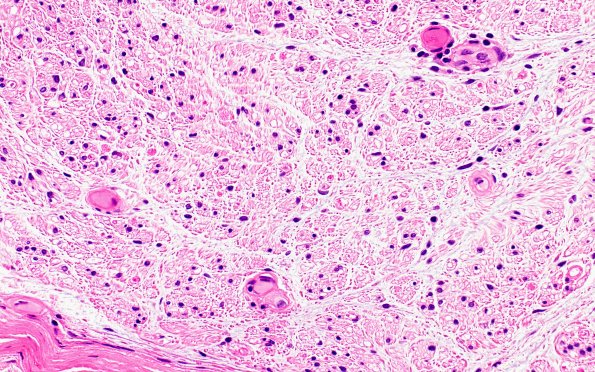

5A3 (Case 5) H&E 40X 3

A few lymphocytes or macrophages surrounded one vessel. (H&E)